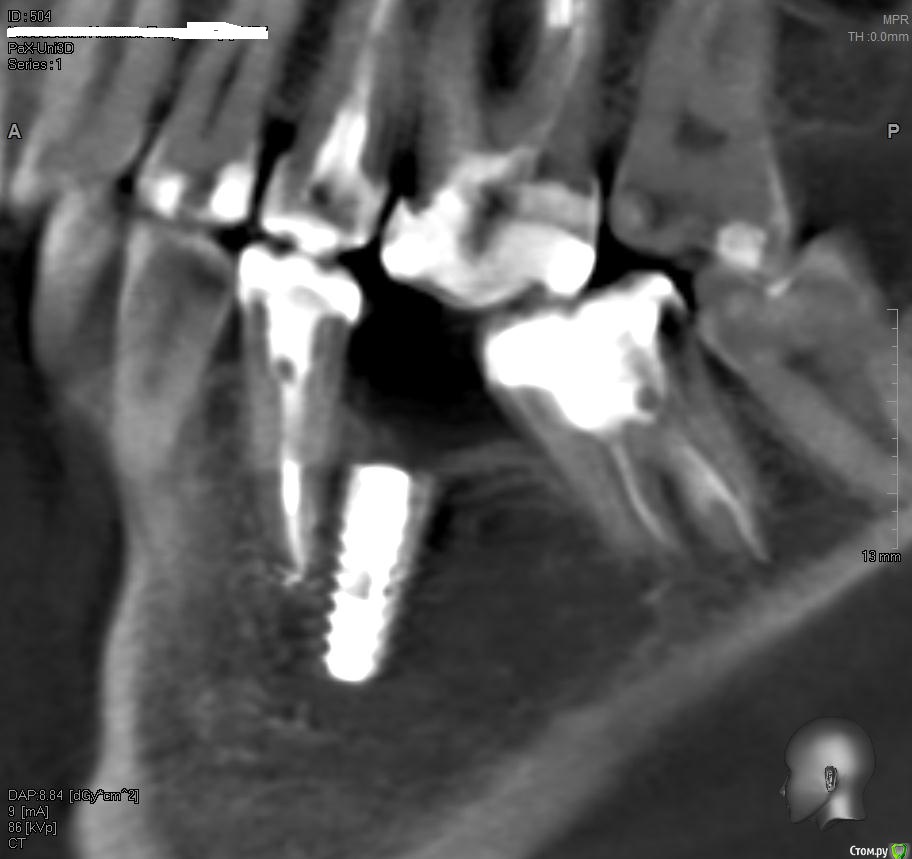

АнтонТЛТ Опубликовано 13 июня, 2015 Поделиться Опубликовано 13 июня, 2015 Сделайте кт, может апексы имплантата с зубом под разными углами 2 Ссылка на комментарий

MotorDantist Опубликовано 13 июня, 2015 Поделиться Опубликовано 13 июня, 2015 Сделайте кт, может апексы имплантата с зубом под разными угламиПОДСКАЖИТЕ - У меня месяц назад была аналогичная ситуация! около недели пациент жаловался на боль при накусывании потом боль прошла. КАКАЯ перспектива? Ссылка на комментарий

Kovalov Igor Опубликовано 16 июня, 2015 Поделиться Опубликовано 16 июня, 2015 А здесь есть показания? а кт не делали? ))) вопрос чувствую с загвоздкой Ссылка на комментарий